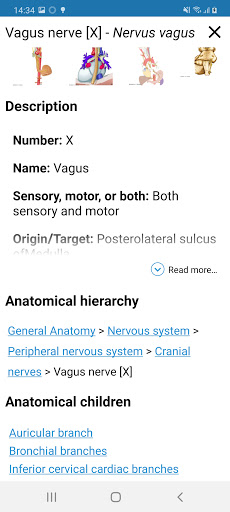

- Ketuk label untuk menampilkan struktur anatomi

*Peningkatan tampilan detail bagian anatomi untuk memudahkan identifikasi dalam gambar modul saat ini dan modul lainnya.

tampilan detail istilah terkait struktur anatomi sekarang ditampilkan

-Dalam tampilan detail struktur anatomi , pin sekarang menunjukkan struktur terkait di semua gambar yang ada